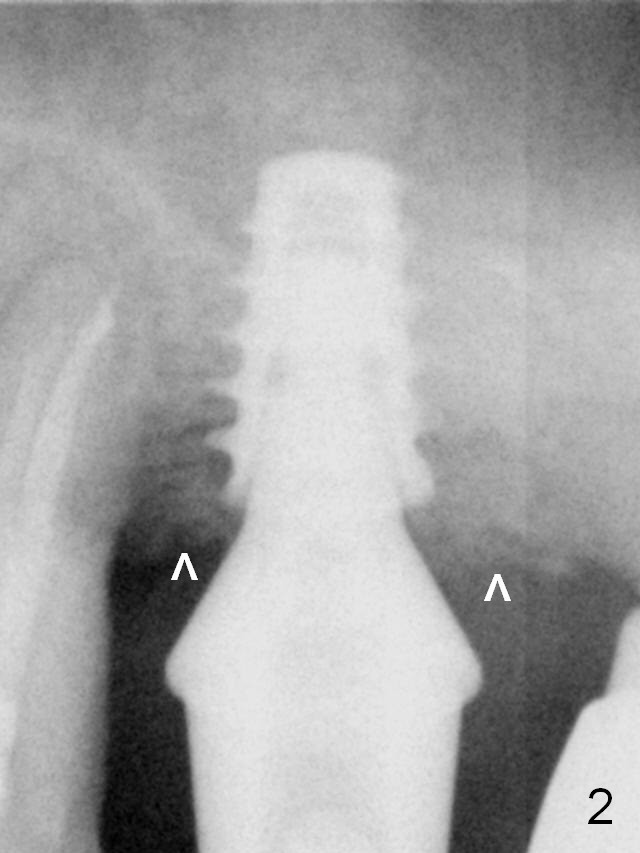

Collagen plug is used to repair the perforation before placing a short (5x7 mm) IBS implant with ~ 25 Ncm (Fig.2). After placing a 6.5x5.7(3) mm abutment, allograft is placed around the most coronal exposed implant thread (^).